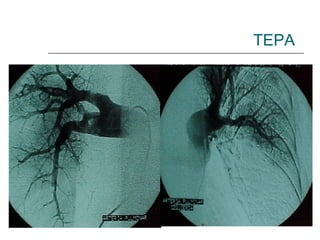

TEPA ANGIOGRAFÍA PULMONAR Es el  gold standard  del diagnóstico de embolismo pulmonar, pero tiene limitaciones. Debe ser interpretada por un experto y es i nvasiva , por lo que queda reservada para un grupo reducido de pacientes en los cuales el diagnóstico no puede ser establecido por métodos menos invasivos, y la sospecha diagnóstica persiste. Peter F. Fedullo, Victor F. Tapson. “the evaluation of suspected Pulmonary embolism”. The NewEngland Journal of Medicine, vol349:1247-1256, september 25, 2003 Gregory Piazza, Samuel Goldhaber “Acute Pulmonary Embolism: Epidemiology and Diagnosis” Circulation. 2006;114:e28-e32.

TEPA